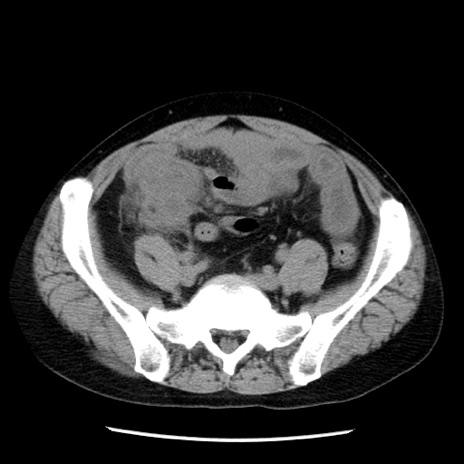

症例29(横断像)

【症例】40歳代男性

【現病歴】2日前から胃痛あり。徐々に周期的な激痛に変化した。本日になっても激痛があるため受診。

【身体所見】意識清明、BT 38-39℃台あり、腹部:膨満、やや硬、右下腹部に圧痛あり。

【データ】WBC 8500、CRP 23.26